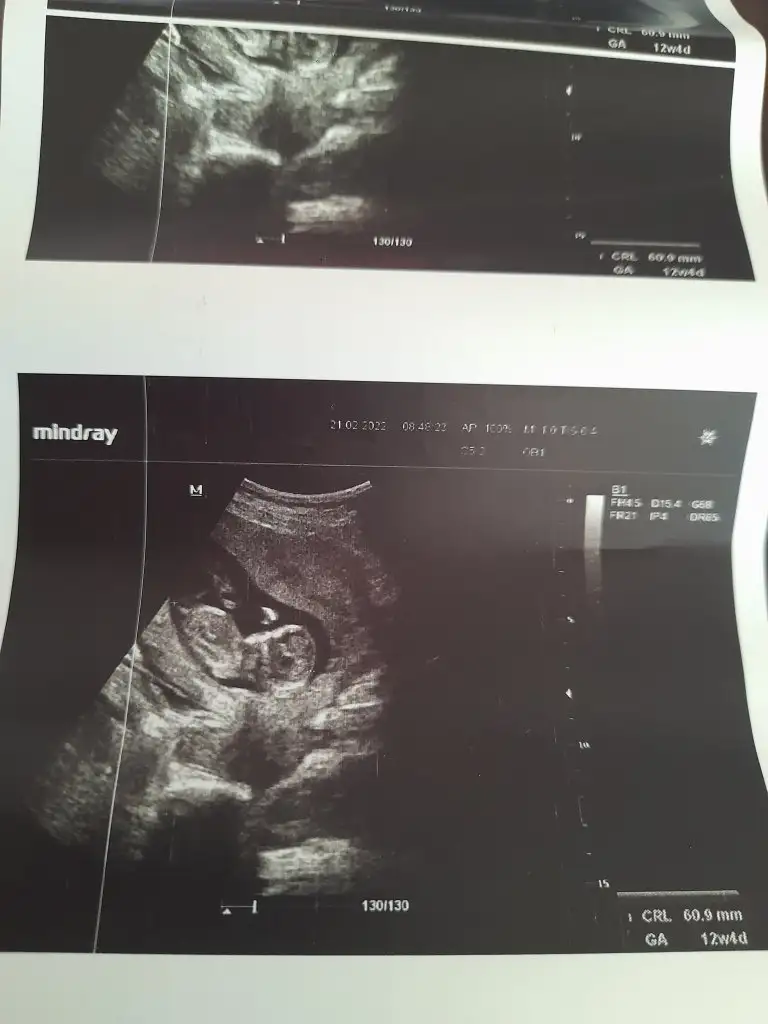

Merhaba 12+4 haftalık nub teorisi ile tahminde bulunabilir misiniz. Teşekkür ederim.

• 20220221_100239.webp

20220221_100239.webp

14,2 KB · Görüntüleme: 88

Buda diğer fotoğraf nub teorisi tahmin ıstiyorum yardımcı olur musunuz

Eklentiler

• 20220221_100310.webp

20220221_100310.webp

18,5 KB · Görüntüleme: 73

• 20220221_092239.webp

20220221_092239.webp

26,9 KB · Görüntüleme: 67